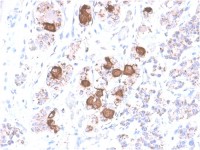

IHC-P analysis of human breast carcinoma using GTX81488 Cathepsin K antibody, Internal.